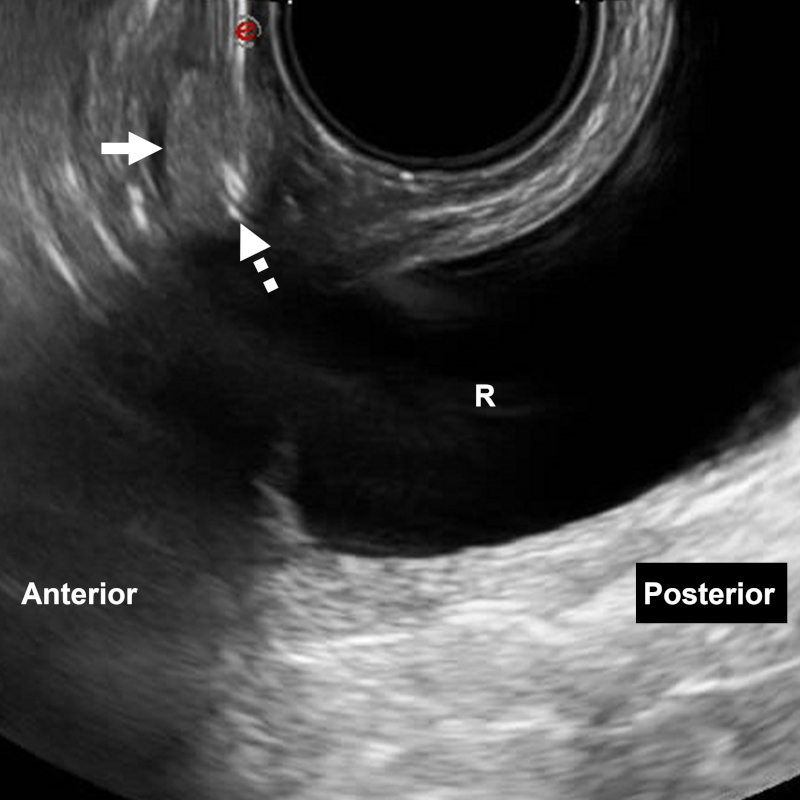

Las lesiones paravaginales, perirrectales o prostáticas también podrán ser intervenidas en forma transvaginal (Fig. 22) o transrectal (Fig. 23). En ambos casos deberá contarse con medidas higiénicas adicionales y preparación antibiótica previa. Si el acceso es transvaginal, se podrá usar anestésico tópico o vaginal submucoso inyectable. Sin embargo, esta técnica puede resultar incómoda. Las biopsias transrectales suelen ser mejor toleradas que las transvaginales28,29,33,34.

Figura 22

Mujer de 40 años con antecedentes de cáncer de recto y nódulo rectal-vaginal en control oncológico. Biopsia transvaginal directa (flecha discontinua) bajo ecografía: nódulo (flecha). R: recto. Aguja utilizada: Franseen 18 G. Diagnóstico final: carcinoma seroso de bajo grado.